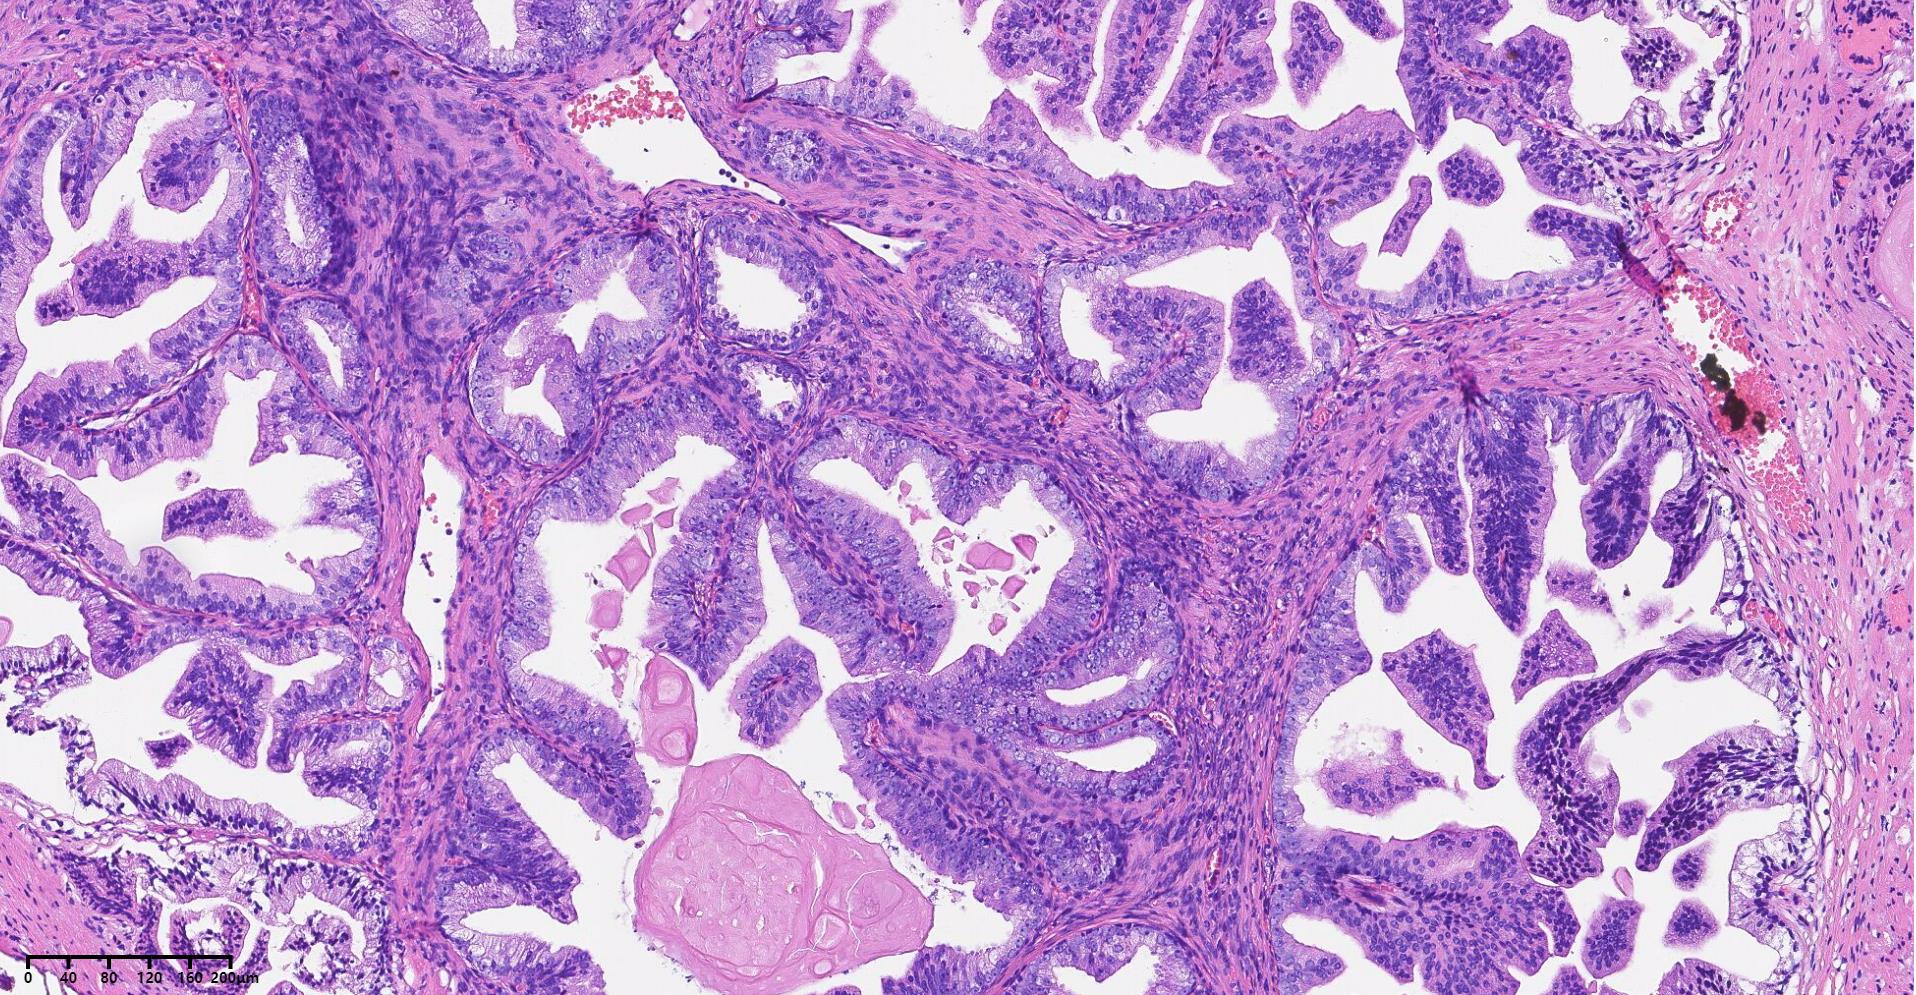

前列腺PIN?

发现肉眼血尿5月余,PAS 5.7

经尿道前列腺等离子电切组织

本例核仁巨大,值得关注!

嗜酸性大核仁,胞浆透亮,PIN没问题。还是组化一下吧,